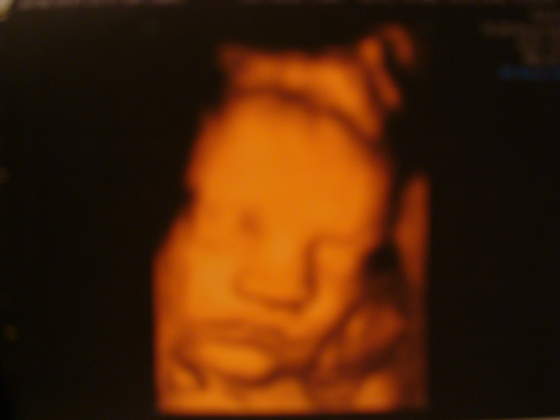

a oto mój słodziak:

nasz Mateusz waży 3010g w 34tyg i 1 dzień![]()